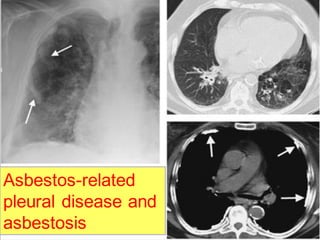

Rule no. 2

Asbestos-related

pleural disease and

asbestosis

Associated pleural thickening and/or

calcification suggest asbestosis.

Rule no. 5